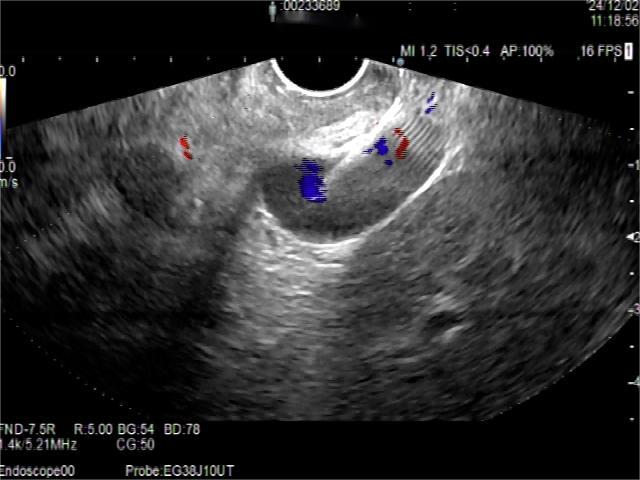

• 超声内镜引导下胃旁曲张静脉精准断流术治疗食管胃静脉曲张出血的疗效分析(附20例报告)

2025, 31(8):85-90. DOI: 10.12235/E20250036

摘要 (153) HTML (42) PDF 5.38 M (98) 评论 (0) 收藏

摘要:目的 探讨超声内镜引导下胃旁曲张静脉精准断流术治疗食管胃静脉曲张出血的疗效。方法 回顾性分析2024年1月1日-2024年12月31日于该院接受超声内镜引导下胃旁曲张静脉精准断流术治疗的20例肝硬化食管胃静脉曲张出血患者的临床资料,并评估治疗效果。结果 20例患者均顺利完成超声内镜引导下胃旁曲张静脉精准断流术;注射组织胶联合置入弹簧圈(16例)和单独注射组织胶(4例)均成功阻断胃旁来源的曲张静脉;所有患者均未发生穿孔、食管贲门狭窄、大出血、败血症和异位栓塞。1例单独注射组织胶的患者,术后胃旁曲张静脉少许渗血,经降低门静脉压力治疗3 d后好转,另1例单独注射组织胶患者,术后出现低热,抗感染3 d后体温恢复正常。结论 超声内镜引导下胃旁曲张静脉精准断流术治疗食管胃静脉曲张出血的临床疗效好,异位栓塞、大出血、感染和穿孔等并发症少,但仍需要密切随访,观察胃旁曲张静脉的排胶问题。